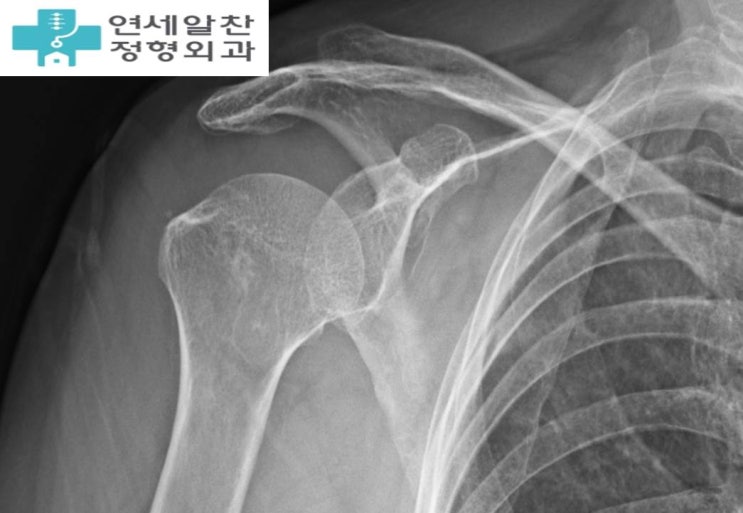

Supraspinatus Repair and Biceps Tenotomy for Supraspinatus Tear with Long Head of Biceps Tear

#supraspinatus tear#biceps tendon tear#supraspinatus repair#biceps tenotomy#arthroscopy